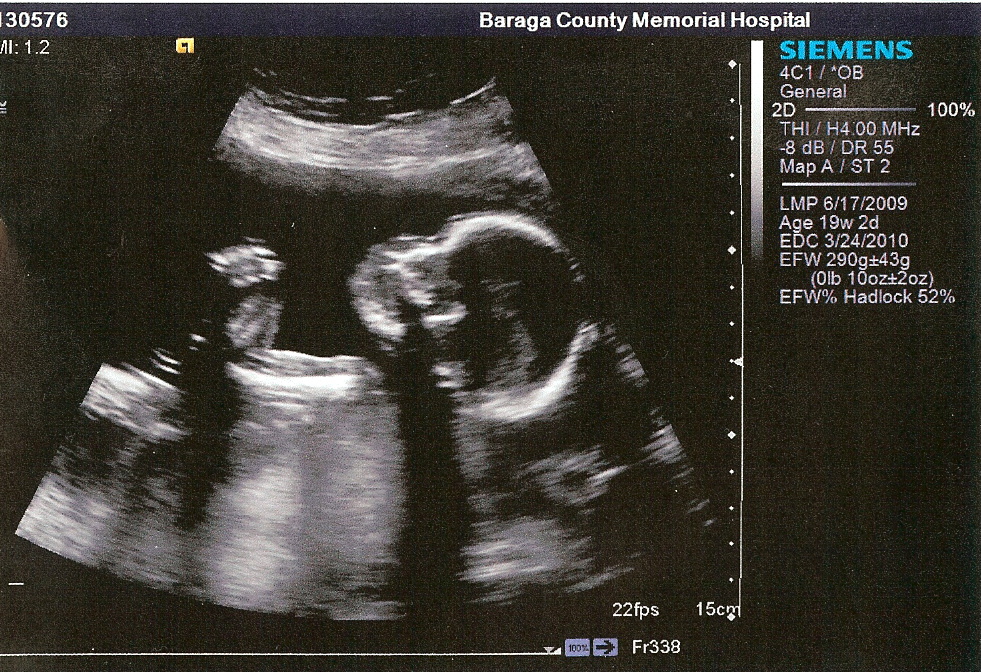

Hi, my name is Samuel Ezra Salo! I was in my Mommy's tummy for quite awhile. I got out of her tummy on March 17, 2010 at 4:54pm. (I didn't have my watch on so I cannot confirm the time.) Daddy and Mommy tell others I was 10 pounds 3 ounces and was 21 1/2 inches long when I came out of my Mommy's tummy. I don't know what that means but will probably figure out someday. For now I will just hang out with Daddy and Mommy.